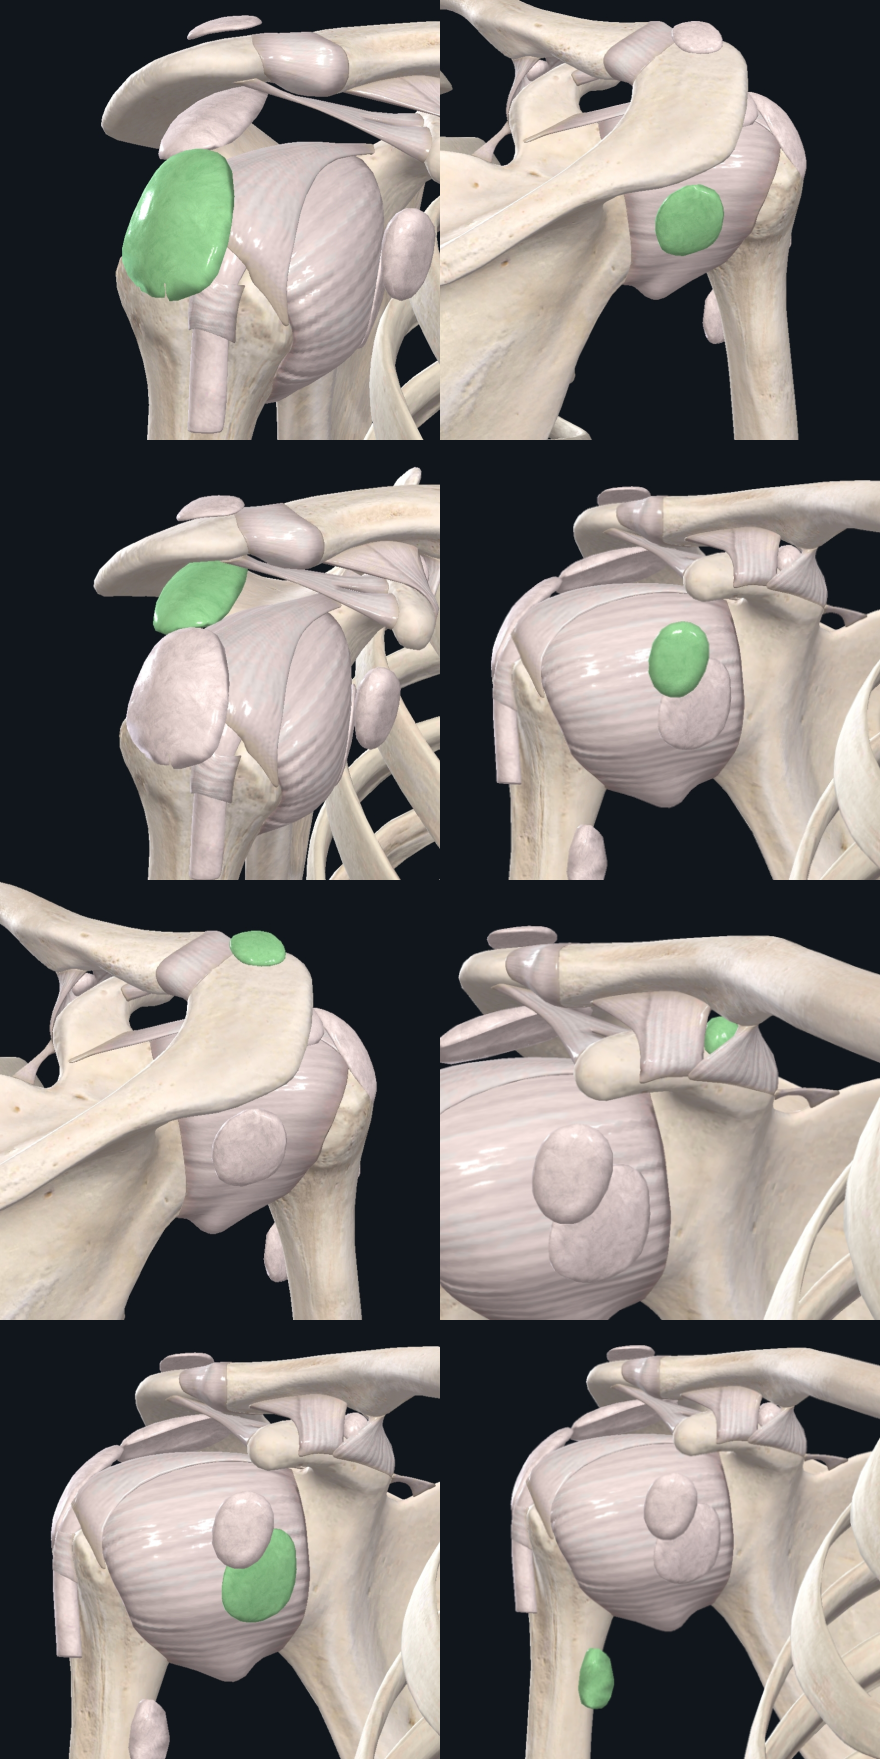

Shoulder Bursae Anatomy

From top left, clockwise. Subdeltoid Bursa, Infraspinatus Bursa, Coracobrachachial Bursa, Coracoclavicular Bursa, Teres Major Bursa, Subscapular Bursa, Subcutaneous Acromial Bursa and Subacromial Bursa.

Bursae of the Shoulder

The 6 Bursae of the shoulder are:

Subdeltoid Bursa: Permits smooth movement of the rotator cuff deep into the Coracoacromial arch.

Subacromial Bursa: Lessens friction and ensures smooth movement of the Supraspinatus tendon deep into the Subacromial space.

Subcutaneous Acromial Bursa: Protection of the Acromion.

Subscapular Bursa: Lessens friction between the Subscapular tendon and the shoulder capsule, Coracoid process and the Scapula neck.

Infraspinatus Bursa: Lessens friction between the Infraspinatus tendon and the shoulder capsule.

Coracobrachachial Bursa: Lessens friction between the Coracobrachialis tendon and the Coracoid process of the Scapula.

Other Bursae exist around the area of the shoulder.

Coracoclavicular Bursa: Lessens friction between the Coracoclavicular ligament and the Clavicle.

Teres Major Bursa: Lessens friction between the Teres Major and Latissimus Dorsi tendons.